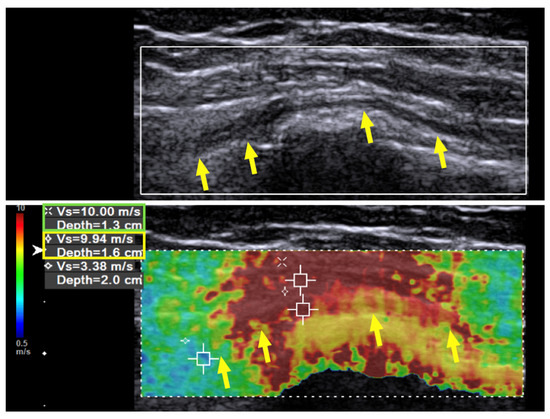

Immediately after the hydrodissection, the SWV was decreased temporarily due to the artifact of the injectate that infiltrated the soft tissue. The neuropathic pain was decreased from a VAS score of 8 to 2, and the patient experienced a sensation of local fullness. There was no muscle-power change immediately after the hydrodissection. When followed up two months after the last hydrodissection, the neuropathic pain had decreased from a VAS score of 8 to 3 (out of 10). The muscle power of the wrist extensors had considerably improved from 1 to 4 (on a scale of 0 to 5, with 5 being normal), and that of the finger extensors improved from 1 to 3. Neurodiagnostic studies revealed MUAPs over the supinator, ECRL, and EDC muscles, but MUAP remained absent over the EIP. US of the radial nerve still showed swelling and hypoechoic changes in the fascicles, as had been observed prior to treatment. However, the hardness of the surrounding tissue had decreased from 10.0 m/s to 7.45 m/s and in some areas even to 6 m/s (Figure 3, green box). The radial nerve hardness had decreased from 9.94 m/s to 8.62 m/s (Figure 3, yellow box).

Figure 3. Case 1: Shear wave velocity after hydrodissection. Shear wave velocity (SWV) investigation of the radial nerve (long axis) over the spiral groove after triple hydrodissection in a 31-year-old man with wrist drop following plate removal after humerus fracture osteosynthesis. After triple hydrodissection, the hardness of the scar (green box) and radial nerve (yellow box) over the spiral groove has decreased. Yellow arrow: radial nerve in longitudinal view.